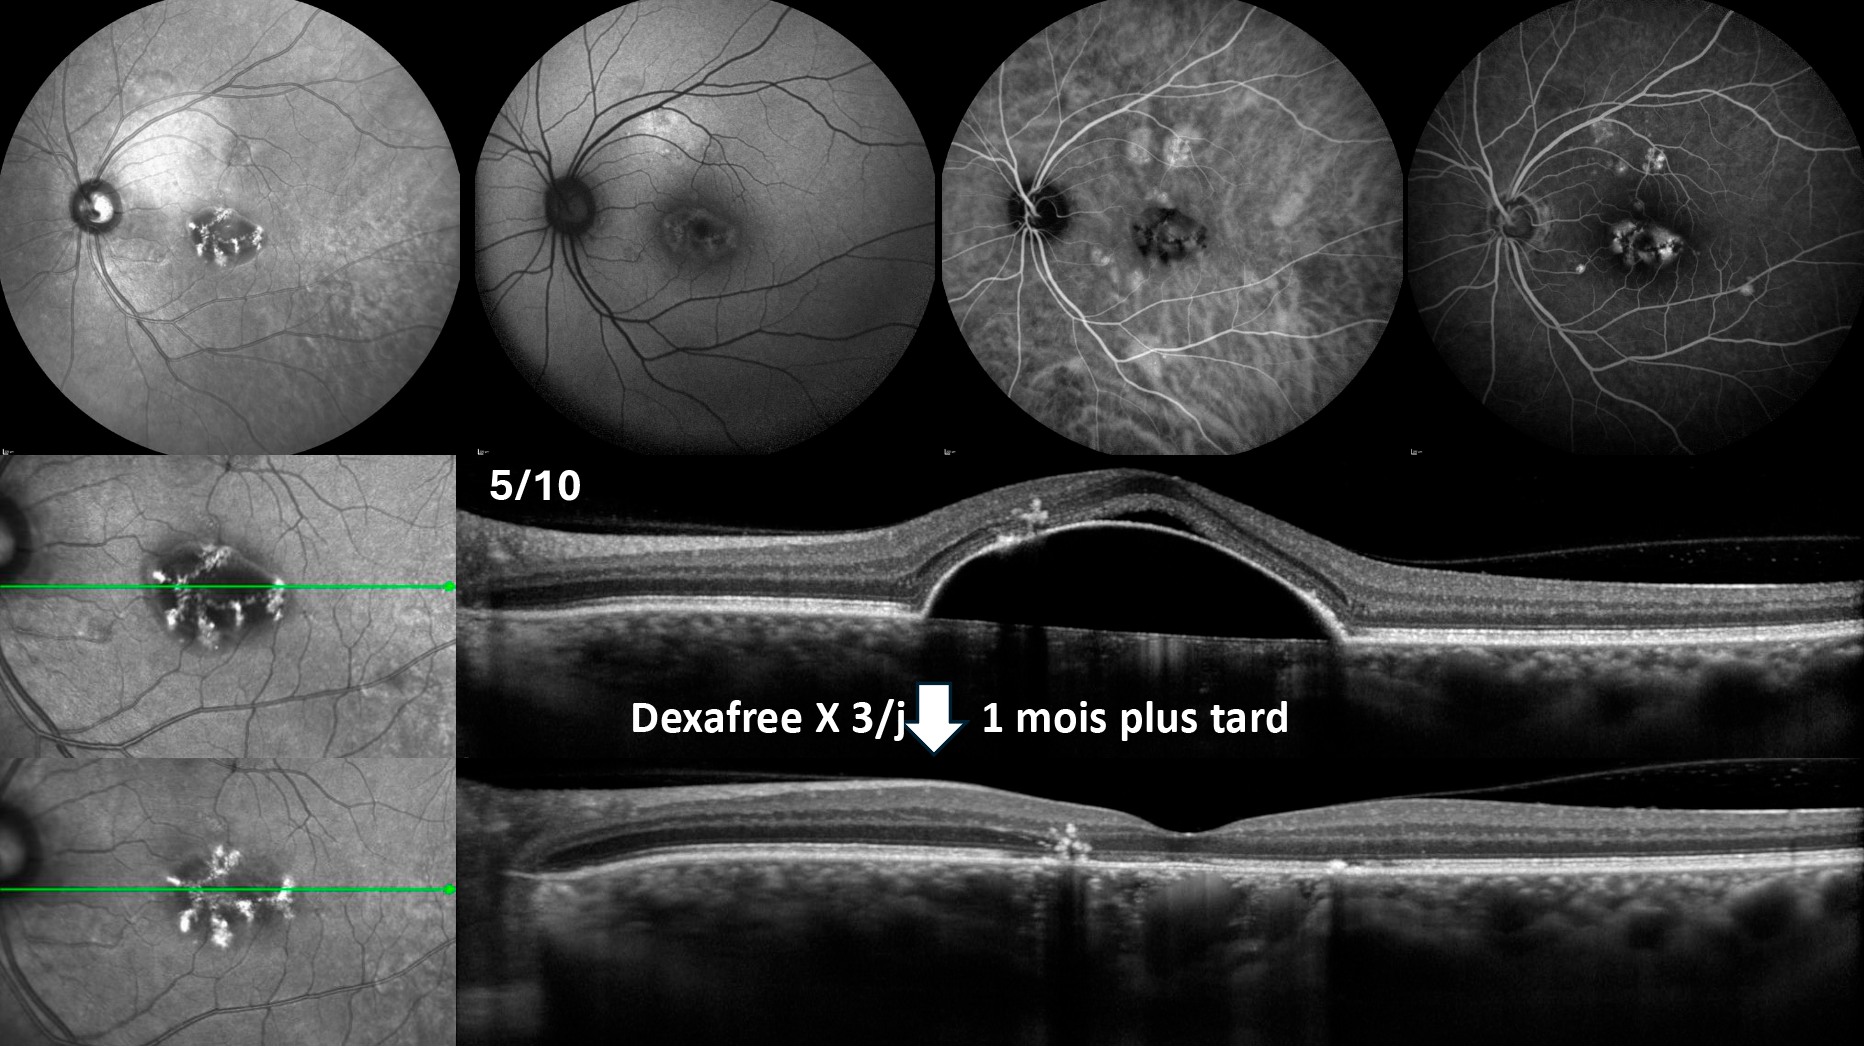

Néovaisseau du myope fort : ne pas méconnaître une choroïdite multifocale ou une choroïdite ponctuée interne et savoir quand démarrer un immunosuppresseur